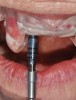

From the data and collaboration in steps 1 through 3, surgical guides can be fabricated for static surgery, and when indicated, prosthetic components, such as custom healing abutments, provisional crowns, or fixed partial dentures, can be produced for delivery at the time of surgery to guide soft-tissue healing. The static approach, better known as computer-guided surgery, refers to the use of tissue-tooth or soft- and hard-tissue-supported surgical templates. In essence, the virtual implant position planned from the CBCT, IOS, and face-in data sets is reproduced. The guide is produced with master cylinders (portals) through which the osteotomy preparation drills are introduced, and in full-guidance cases, the delivery of the implant is carried out (Figure 14 and Figure 15). Dynamic guided surgery or computer "navigation" traces the virtual implant position directly from CBCT data and employs motion tracking or real-time tracking technology to prepare the implant osteotomy. This makes it possible to determine the actual position of the surgical drill on the reconstructed 3D image provided by the CBCT. The surgeon is guided to the position that was planned preoperatively while he or she performs the surgical procedure. Examples of dynamic navigation systems are Navident (ClaroNav, claronav.com), X-Guide Dynamic 3D Navigation (X-Nav, x-navtech.com), Image Guided Implant (IGI) Dentistry System (Image Navigation, image-navigation.com), Inliant® (Navigate Surgical, navigatesurgical.com), and YOMI®, a robotic haptic guidance system (Neocis, neocis.com).

Guided surgery, whether it be static or dynamic navigation, improves accuracy in comparison to free-handed implant placement procedures.8,9 Static surgery may involve the use of laboratory-processed stereolithographic guides to both prepare the osteotomies and deliver implants.10 Other than in regions with limited access, these accurate guidance templates can be considered for use in any scenario. Dynamic navigation offers advantages in these types of situations. Although linear and angular deviations between planned and executed implant positions are possible and probable, operator experience and use of appropriate hardware can minimize these deviations.11,12